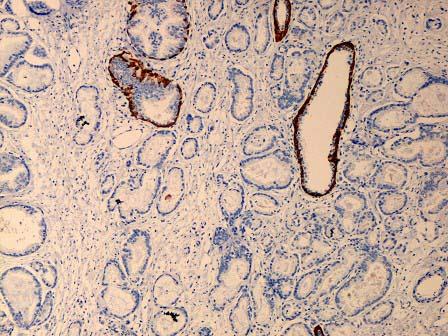

问题 男性,78岁,排尿不畅,腰腿痛4个月,经直肠彩超引导下前列腺穿刺活检,显微镜下见腺体结构紊乱,形状大小不一(如图),细胞有异型,核仁显著,腺体外层基底细胞消失,免疫组化P63染色如图,该患者应诊断为 ( )

选项 A.慢性前列腺炎 B.前列腺结节样增生 C.前列腺低级别上皮内瘤变 D.前列腺高级别上皮内瘤变 E.前列腺癌

答案 E